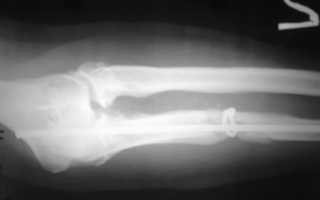

Решающее значение для диагностики ложного сустава имеет рентгенологическое исследование.

Для того чтобы определить наличие патологии, в обязательном порядке делают несколько снимков в разных проекциях: две перпендикулярные и дополнительные косые. На снимках можно увидеть наличие суставной щели между костями, которая имеет неровные очертания. Наиболее широкая щель встречается при гипертрофированном типе образования.

Края костных отломков сглажены, закруглены. Иногда на рентгенографическом снимке можно увидеть, как один из отломков в общих чертах напоминает суставную впадину, а другой похож на головку кости, входящей в эту впадину. Помимо этого костно-мозговая полость, расположенная между ними, зарастает с формированием замыкательной пластинки. Для того чтобы оценить степень и интенсивность происходящих патологических процессов, назначают дополнительное радионуклидное обследование.